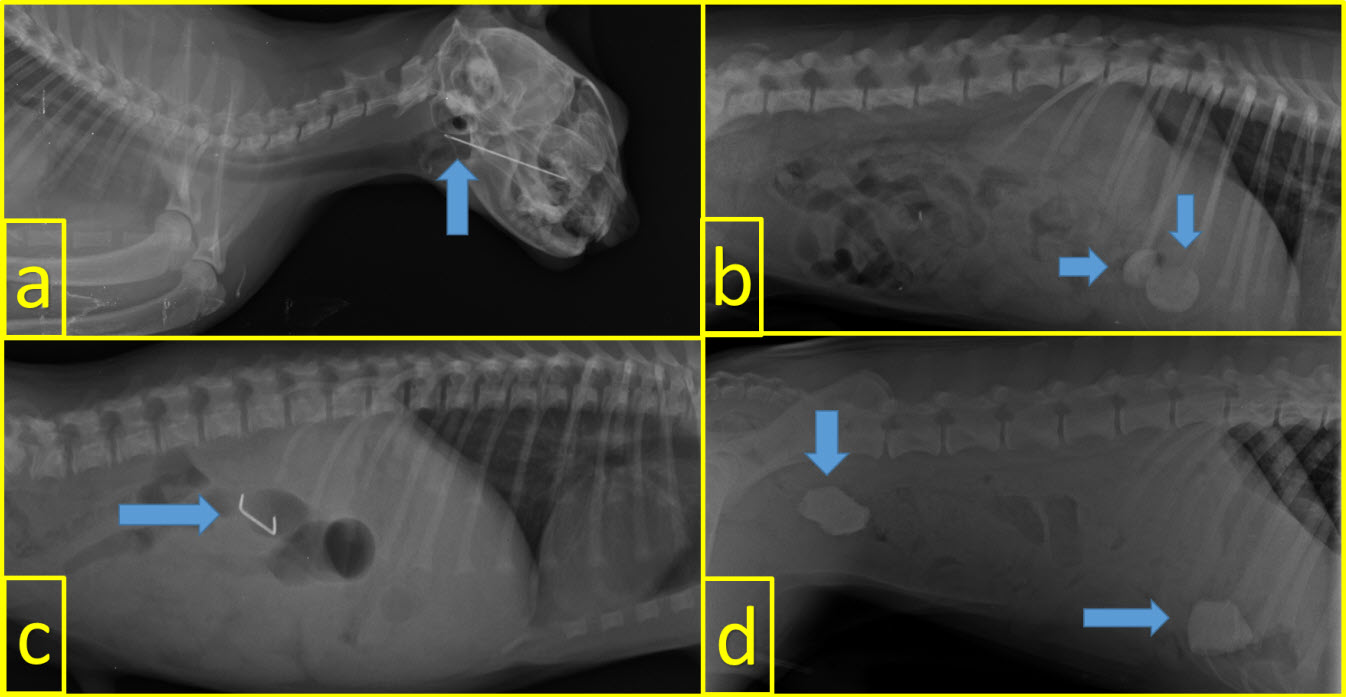

The locations of FB in the gastrointestinal system were as follows: stomach in 14 (43.75 %) animals, small intestine in 10 (31.25 %), esophagus in six (18.75 %), and large intestine in three (9.38 %). FB were detected in both small intestine and large intestines only in one patient. Some of the FB detected by radiography are shown in FIGS 3 and 4.

FIGURE 3. Visualization of some of the Foreing Body by direct radiography. a: sewing needle in a cat, b: two erasers in the stomach in a dog, c: metallic object in a dog, and d: two stones in the stomach and large intestine in a dog